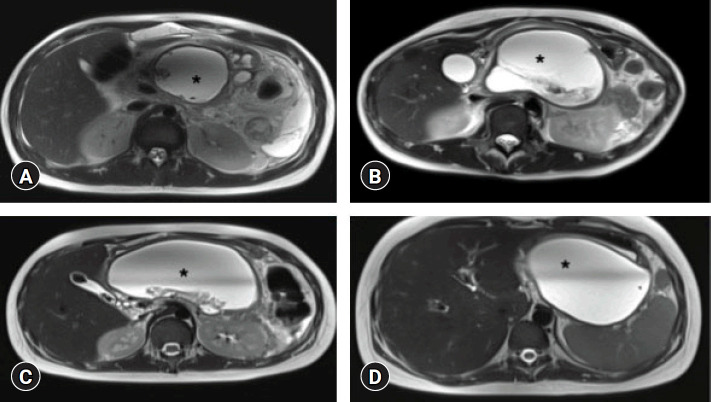

背景/目的:壁状坏死(WON)是儿童急性胰腺炎的严重并发症,其内镜治疗证据有限。本研究评估了超声内镜(EUS)引导下放置腔内金属支架(LAMS)治疗小儿WON患者的疗效和安全性。方法:这项开放标签前瞻性研究纳入了5-18岁继发于急性坏死性胰腺炎的儿童患者,这些患者于2021年1月至2023年7月在三级中心接受eus引导的LAMS治疗。临床成功,定义为12周时症状缓解和WON清除,是主要结局。次要结局包括技术成功、并发症和是否需要额外干预。结果:纳入11例患者,平均年龄15.5±3.1岁。12周内临床成功率90.9%,技术成功率100%。两名患者经历了支架闭塞,并用盐水冲洗处理;1例需要电视辅助腹膜后清创。平均住院时间5.4±3.3天。无重大不良事件报告。结论:eus引导下的LAMS放置是一种安全有效的替代手术治疗小儿WON的方法,具有较高的临床和技术成功率和最小的并发症。需要进一步的多中心研究来验证这些发现。

Background: Walled-off necrosis (WON) is a severe complication of acute pancreatitis in children, with limited evidence on its endoscopic management. This study evaluated the efficacy and safety of endoscopic ultrasonography (EUS)-guided lumen-apposing metal stent (LAMS) placement for WON in pediatric patients.

Methods: This open-label prospective study included pediatric patients aged 5-18 years with WON secondary to acute necrotizing pancreatitis that was managed with EUS-guided LAMS at a tertiary center from January 2021 to July 2023. Clinical success, defined as symptom resolution and WON clearance at 12 weeks, was the primary outcome. Secondary outcomes included technical success, complications, and the need for additional interventions.

Results: Eleven patients (mean age, 15.5±3.1 years) were included. Clinical success was achieved in 90.9% of the patients within 12 weeks, with a 100% technical success rate. Two patients experienced stent occlusions that were managed with saline irrigation; one case required video-assisted retroperitoneal debridement. The mean hospital stay was 5.4±3.3 days. No major adverse events were reported.

Conclusions: EUS-guided LAMS placement is a safe and effective alternative to surgery for pediatric WON, with high clinical and technical success rates and minimal complications. Further multicenter studies are required to validate these findings.